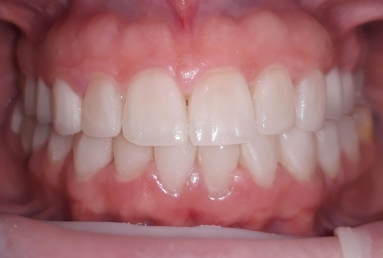

Our patient had general dental abrasion due to maloclusion. After orthodontic treatment, the upper teeth received full ceramic crowns, while the lower were restored with crowns and veneers.

We managed to solve partialy the orthodontic problem and at the same time restore the frontal teeth with esthetic ceramics for a perfect smile.